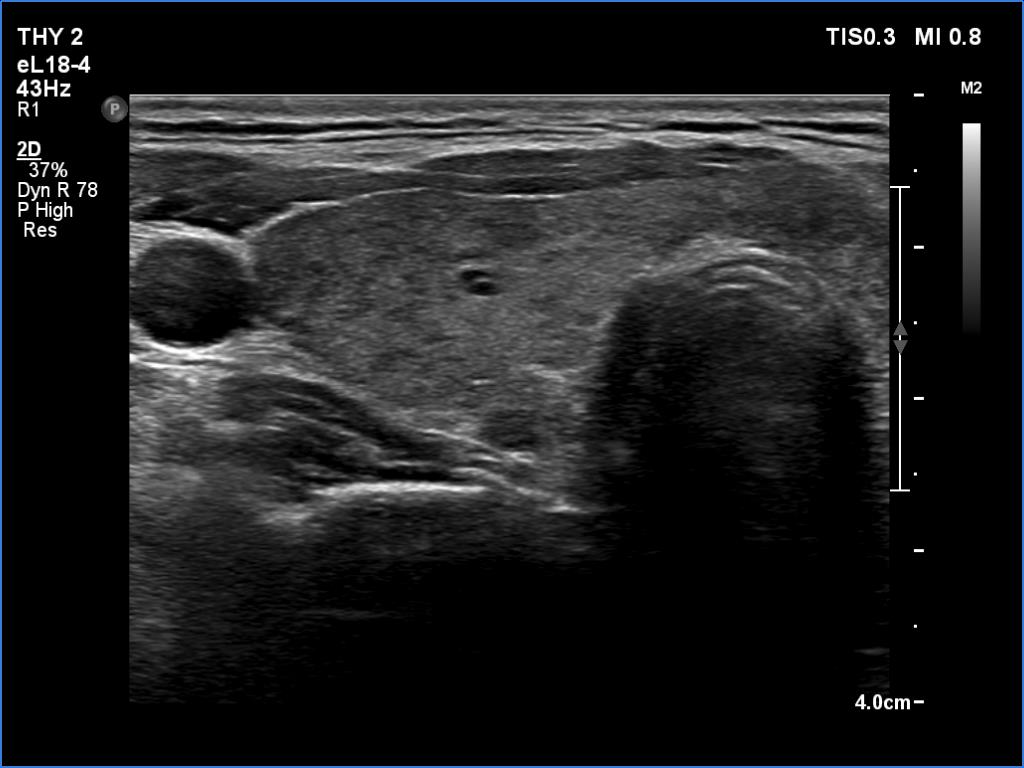

Right lobe, longitudinal scan

Clinical data: A 35-year-old woman was referred for a newly diagnosed hyperthyroidism. The patient had typical complaints, including elevated heart rate and weight loss.

Comment.

This is the typical course of a non-relapsing Graves' hyperthyroidism. As the hormone results improve, both the size of the initially enlarged goiter and the degree of hypoechogenicity decrease.